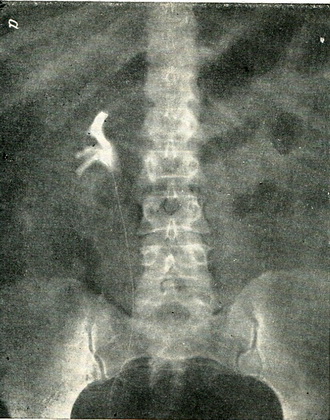

Діагностика уточнюється хромоцистоскопией і особливо пієлографією. При нефроптозі індигокармін виділяється ниркою нормально. Перед пієлографією обов'язково проводиться оглядовий рентгенівський знімок нирки і сечоводу, щоб виключити наявність каменів. Пієлографія проводиться в горизонтальному і у вертикальному положенні, так як на звичайному знімку в лежачому положенні можна не виявити опущення нирки (рис. 126). Пієлограма показує не тільки опущення нирки, але і повороти навколо сагітальній, поперечної та вертикальної осі. При повороті навколо поперечної осі тінь балії коротшає, при повороті навколо вертикальної осі вона стає вузькою, контури чашечок змащуються, іноді майже не помітні.

Рис. 126. Опущення правої нирки. Ретроградна пієлографія, а - в лежачому положенні; б - у стоячому положенні хворого.